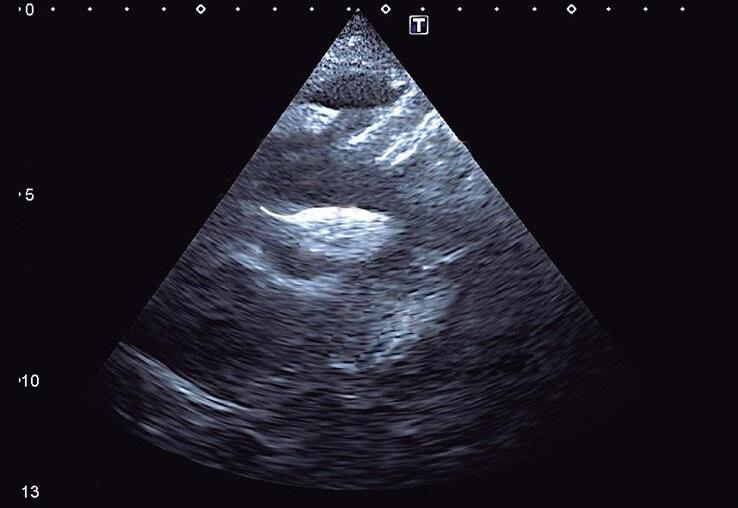

A veia cava inferior (VCI) e a aorta abdominal em eixo curto podem ser visualizadas nesse plano, com o transdutor abaixo do apêndice xifoide do paciente, perpendicular ao abdômen superior e com o index apontado para a esquerda do paciente, na posição de “3 horas” (▶ Vídeo 1-1). Nesse plano, a Ao abdominal é o vaso pulsátil e a VCI varia com a respiração. Em corações normais (situs solitus), a Ao é posicionada à esquerda posteriormente (próximo da coluna vertebral) e a VCI está anterior e à direita (Fig. 1-2; ▶ Vídeo 1-2). Assim, esse plano é importante na identificação do situs e suas anomalias, e alterações da pulsatilidade aórtica (baixo débito sistêmico, lesões Ao obstrutivas, como coarctação da Ao ou arterite de Takayasu). O diafragma também é identificado nesse plano e doenças, como paralisia diafragmática (pós-operatório de cirurgia cardíaca), hérnia diafragmática e derrame pleural, podem ser identificadas.

Fig. 1-2. Plano de abdômen superior: situs atrial e visceral solitus com aorta à esquerda e posterior (mesmo lado do estômago e próxima da coluna, em vermelho) e veia cava inferior (VCI) à direita (mesmo lado do fígado, em azul). A: anterior; P: posterior; C: coluna vertebral; E: lado esquerdo do paciente; D: lado direito do paciente; Ao: aorta.